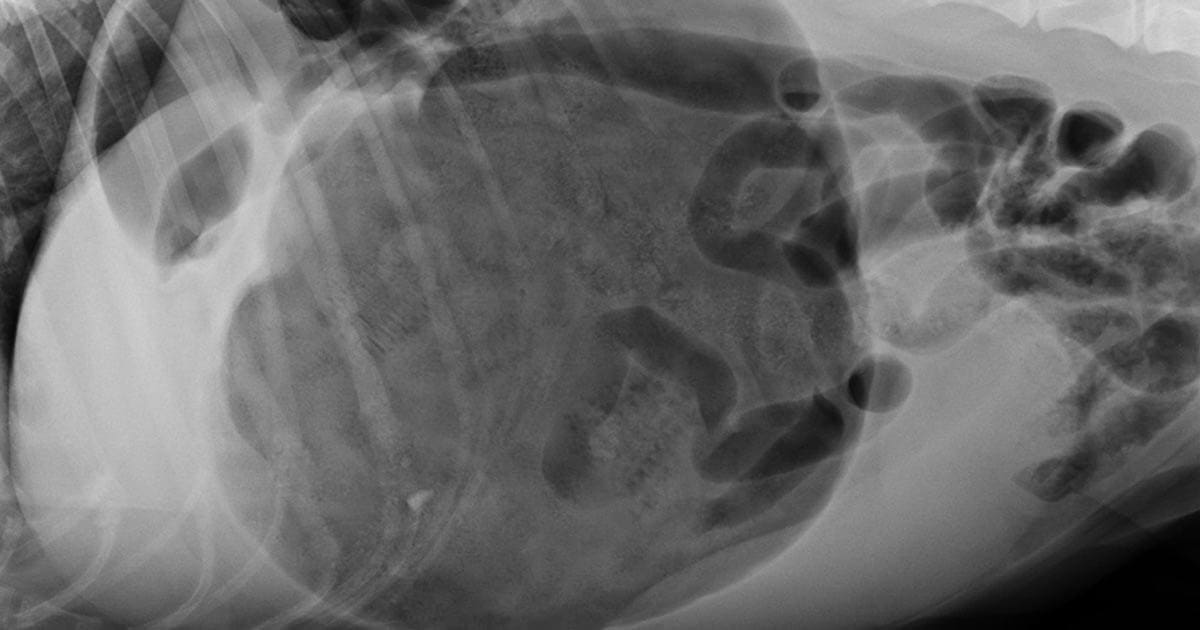

Junior Great Dane 8 months, after neutering and stomach tacking Dog Stomach Tacking During a gastropexy, your veterinarian will surgically “tack” the stomach to the right side of the body wall. Our vet explains whether gastropexy is good for. Gastropexy may be performed either as part of the treatment for gdv or a preventative procedure in dogs at risk of developing the condition. What is a gastropexy in dogs? This condition, known as. Dog Stomach Tacking.